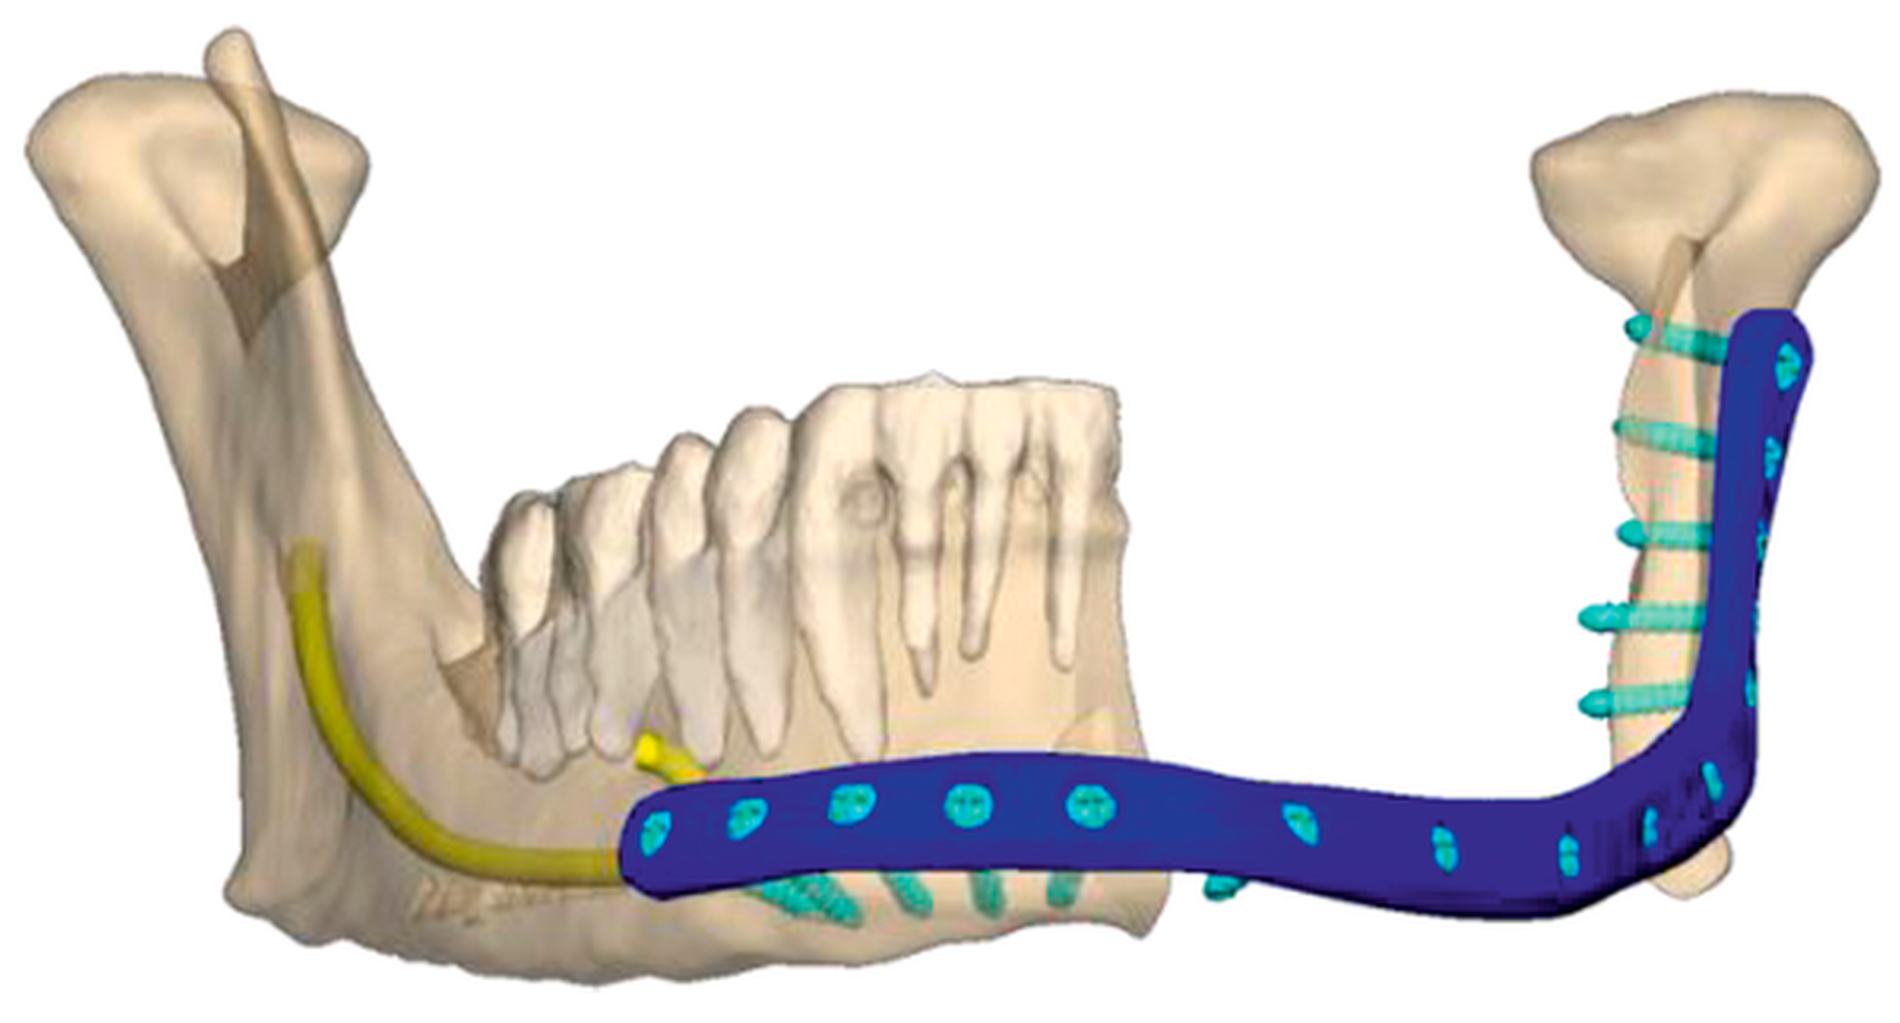

Die prätherapeutische Vorstellung des Patienten in der interdisziplinären Tumorkonferenz ergab das Votum eines primär chirurgischen Vorgehens, wobei sich inzwischen eine Exulzeration des Tumors zeigte (Abbildung 6). In Intubationsnarkose erfolgte daher die radikale Resektion des 10,4 cm großen, gering differenzierten, nicht verhornenden Plattenepithelkarzinoms (pT4a, pN0, G3, V1, Pn0) in Kombination mit einer Unterkieferkontinuitätsresektion (Abbildung 7) sowie einer bilateralen Neck Dissection. Die Rekonstruktion erfolgte mit einer patientenspezifischen Überbrückungsplatte (Abbildung 8) und einem mikrovaskulären Latissimustransplantat. Der weitere stationäre Aufenthalt gestaltete sich unauffällig, der Patient begann zeitnah mit einer Radiotherapie.